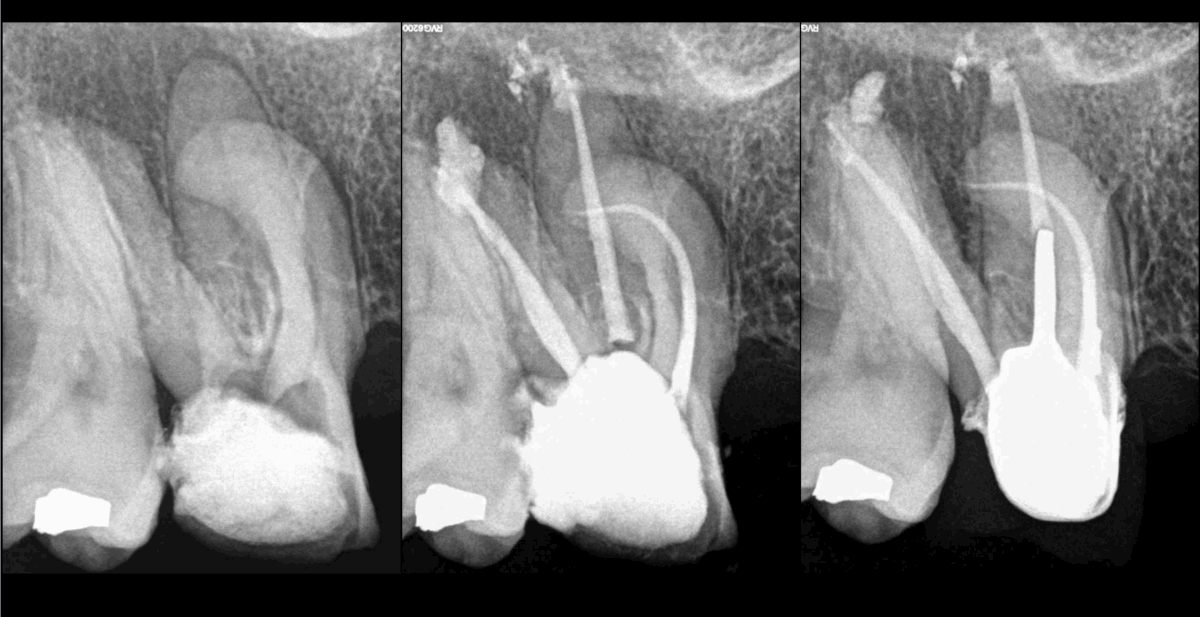

🦷 Lorsque la lésion est accessible à la microchirurgie endodontique, nous recommandons volontiers que la prothèse finale soit réalisée avant que ne soient réalisés les contrôles.

⚠️ Dans le cas contraire (lésion de la racine P), dans ce cas, nous recommandons plutôt d’assurer l’étanchéité de la dent ainsi qu’une couronne provisoire de longue durée (s’il y en a l’indication).